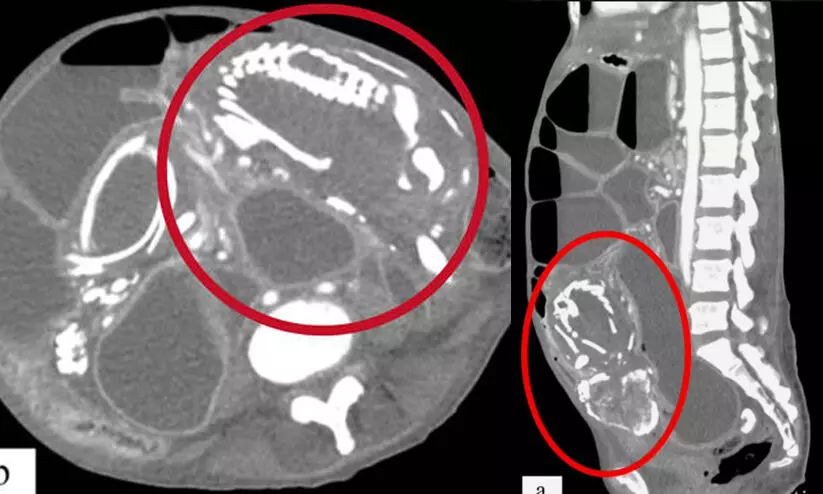

സ്ത്രീയുടെ വയറ്റിൽ വളർന്ന ഭ്രൂണത്തിന് ഒമ്പത് വർഷം മുമ്പ് ടാൻസാനിയയിൽ വെച്ച് തന്നെ ജീവൻ നഷ്ടമായിരുന്നു. കടുത്ത വയറുവേദനയും അസ്വസ്ഥതകളും മറ്റ് ഉദരരോഗങ്ങളും അനുഭവപ്പെട്ടെങ്കിലും അജ്ഞതയും ഭയവും കാരണം ഇവർ കൃത്യമായ ചികിത്സ തേടിയില്ല. പിന്നീട് യു.എസിൽ കുടിയേറിയ ശേഷം നടത്തിയ പരിശോധനയിലാണ് വയറ്റിൽ 'ലിത്തോപീഡിയൻ' ആണെന്ന് കണ്ടെത്തിയത്. ശസ്ത്രക്രിയയിലൂടെ ഇത് പുറത്തെടുക്കണമെന്ന് ഡോക്ടർമാർ നിർദേശിച്ചെങ്കിലും, ശസ്ത്രക്രിയയോടുള്ള ഭയം കാരണം ഇവർ തയാറായില്ല. രോഗം കലശലായതോടെ മലവിസർജനം ഉൾപ്പെടെ തടസപ്പെടുകയും കടുത്ത പോഷകാഹാരക്കുറവും മറ്റ് അസുഖങ്ങളും കാരണം സ്ത്രീ മരിക്കുകയായിരുന്നുവെന്ന് അധികൃതർ വ്യക്തമാക്കി.

ലോകത്ത് ഇതുവരെ 300ൽ താഴെ ലിത്തോപീഡിയൻ കേസുകൾ റിപ്പോർട്ട് ചെയ്തതായാണ് കണക്ക്. ജീവൻ നഷ്ടമാകുന്ന ഭ്രൂണത്തെ ശരീരത്തിന് തിരികെ ആഗിരണം ചെയ്തെടുക്കാൻ കഴിയാതെവരുമ്പോൾ, ശരീരത്തിലെ രോഗപ്രതിരോധ സംവിധാനം ഇതിനെ പുറത്തുനിന്ന് എത്തിയ വസ്തുവായാണ് കണക്കാകുക. തുടർന്ന് ഇതിന്റെ മേൽ കാൽസ്യം നിക്ഷേപം നടക്കുകയും ഭ്രൂണം കല്ലിന് സമാനമായ അവസ്ഥയിലേക്ക് മാറുകയും ചെയ്യുന്നു.